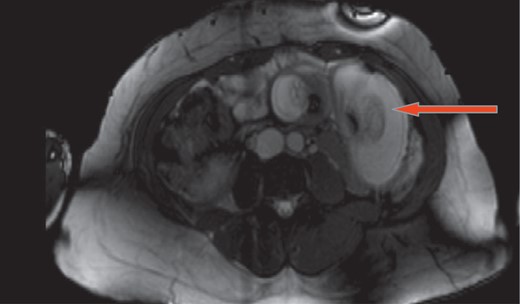

A 37-year-old 6 weeks pregnant female status post-LRYGB 2 years ago presented with 4 hours history of sudden onset of epigastric and peri-umblical pain and tenderness, associated with nausea and vomiting. Vitals signs were stable. Labs including white blood cell count, serum chemistry, urinalysis and liver function tests were all within normal limits. Abdominal ultrasound confirmed intrauterine pregnancy. Magnetic resonance imaging revealed intussusception of small bowel with close loop obstruction (Figs. 1 and 2). Following initial resuscitation, emergent laparoscopy was performed which confirmed the diagnosis. Intra-operatively significantly dilated loop of jejunum approximately 20 cm in length was noticed close to the jejuno-jejunostomy with retrograde telescoping of the jejunum (Fig. 3). At that time decision was made to covert to open laparotomy with resection of irreducible intussusception and reconstruction of jejuno-jejunostomy (Fig. 4). Post-operative course was uneventful, the patient subsequently recovered fully and was discharged home on post-operative day 4. On follow-up, patient was seen in the clinic and reported doing well and pain free. Patient also was following up with her obstetrician to assess the viability of the fetus.

Magnetic resonance imaging shows intussusception of small bowel with close loop obstruction (cross section).